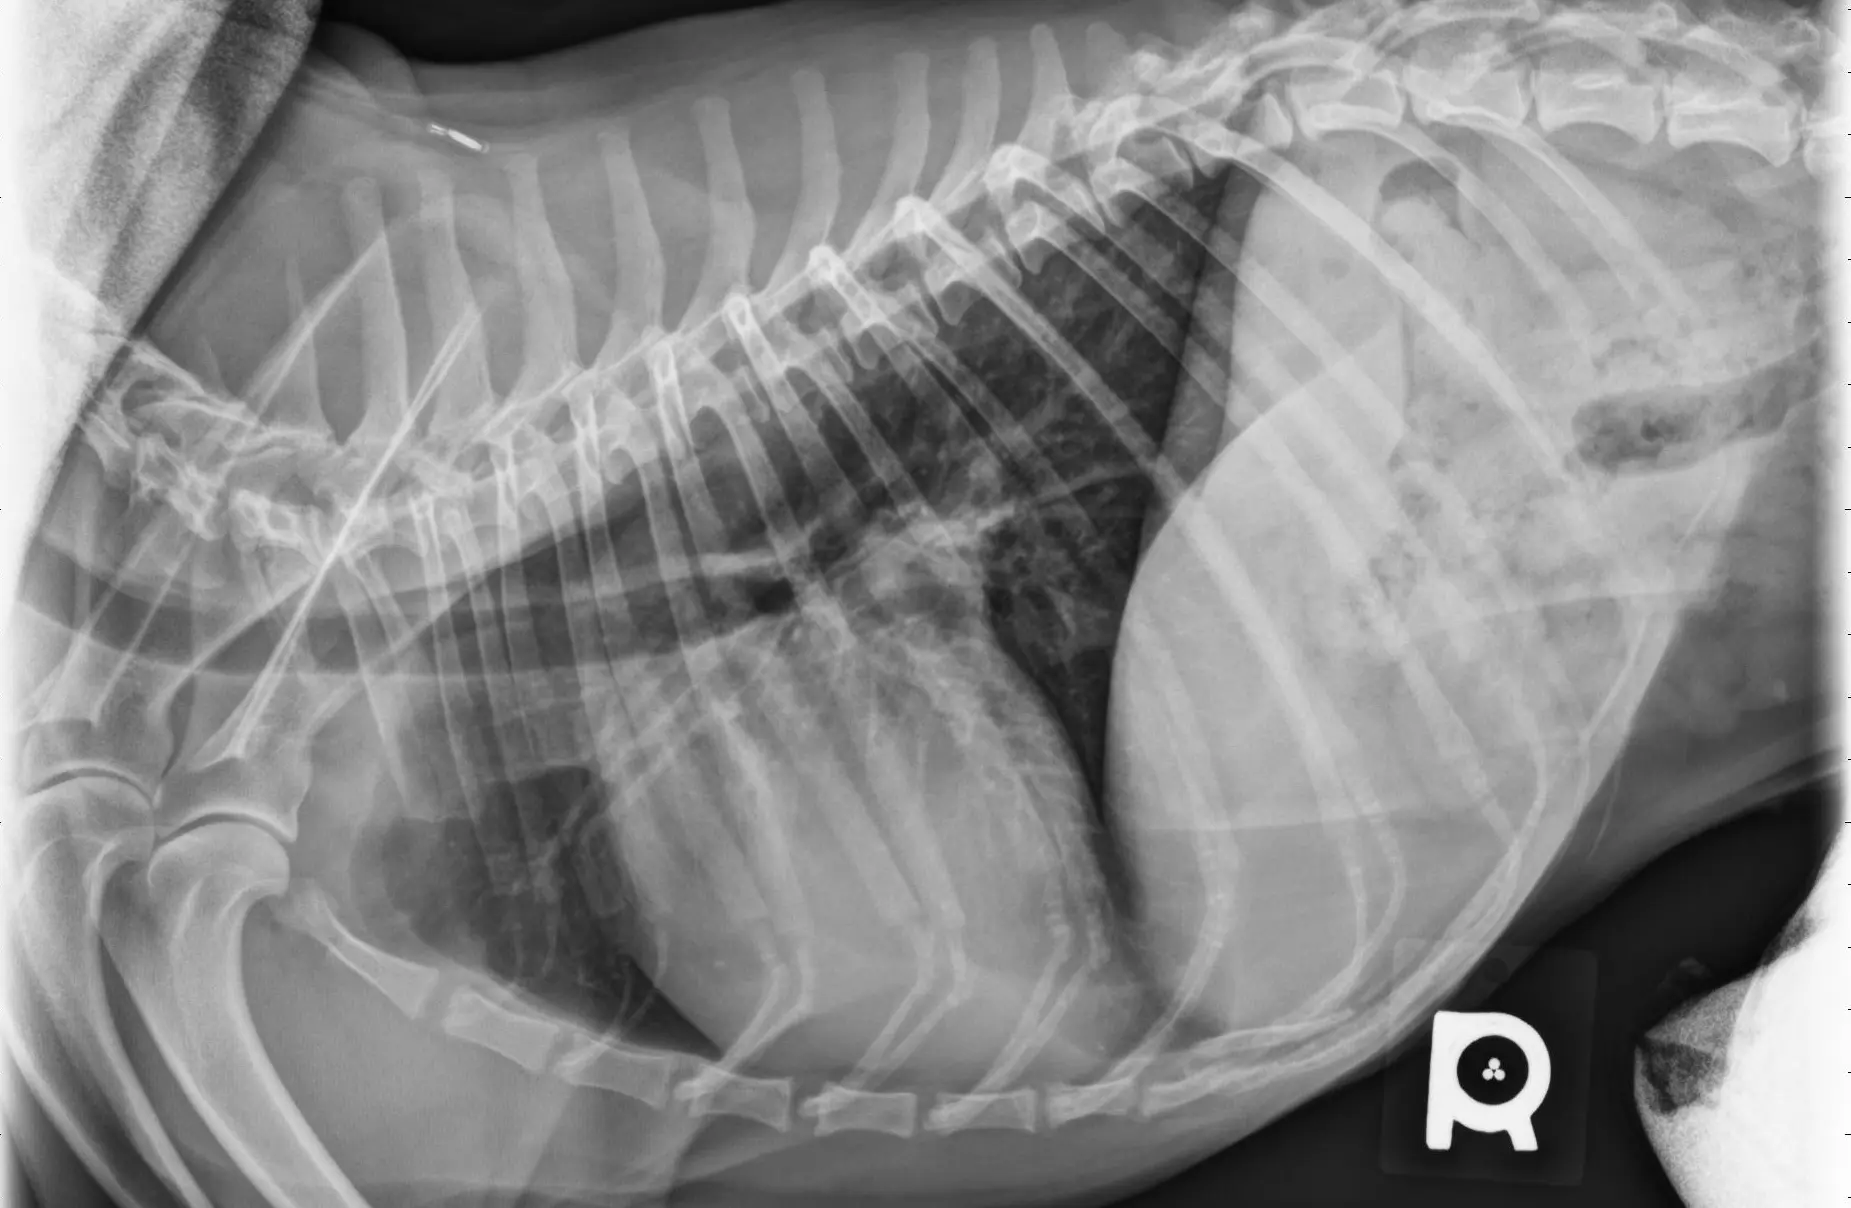

Teleradiology

Teleradiology Services

Our board-certified veterinary radiologist will assist with interpretation of all of the following imaging modalities:

• Radiographs